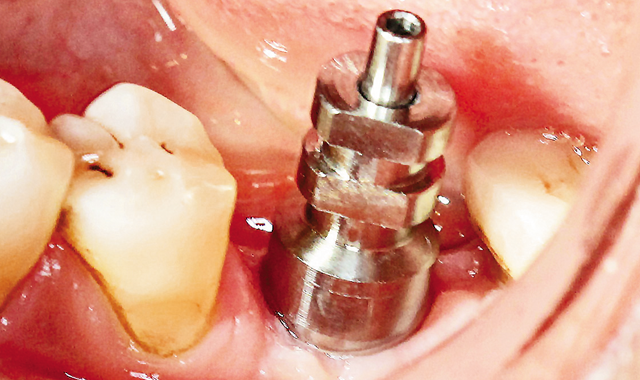

Fig. 11 Open tray impression transfer.

Fig. 12 Taking open tray impression.